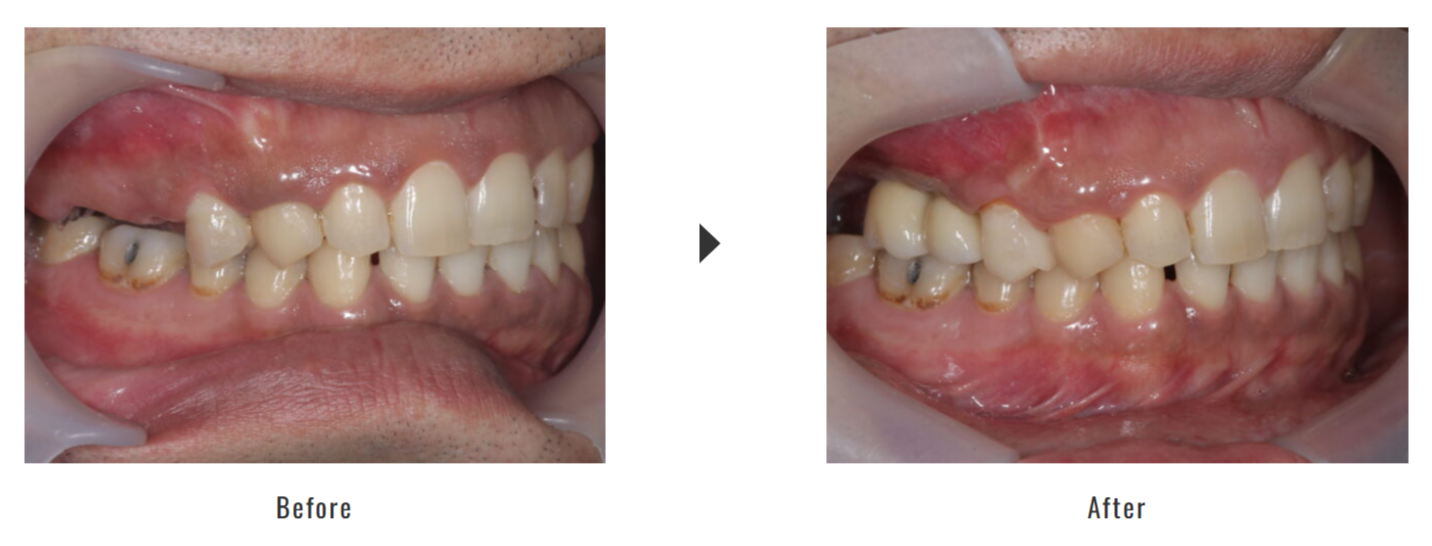

50代男性の症例です。骨の量と幅が不足しており、前歯へのインプラント埋入が困難と判断されました。そこでソケットリフトを併用し、骨を増やしてからインプラントを2本埋入することになりました。

| 施術内容 | 右上前歯部ソケットリフト+インプラント2本+セラミック冠 |

| 治療期間 | 約4〜5ヶ月 |

ソケットリフト:120,000円(税抜) インプラント:500,000円(税抜) チタンアバットメント:80,000円(税抜) セラミック冠:180,000円(税抜) 静脈内鎮静:70,000円(税抜) 合計:950,000円(税抜) ※治療時の価格です。 |

・インプラントは自由診療のため、保険治療と比べて費用負担が高くなります。 ・インプラントと骨が結合する期間が必要なため、治療期間が長くなります。 ・手術後に腫れや軽い痛みを伴うことがあります。 |

| 症例引用元 | 大阪インプラント総合クリニック(梅田茶屋町クローバー歯科:大阪府大阪市北区茶屋町15-22 アーバンテラス茶屋町C棟4階ほか) 06-6485-8701 |